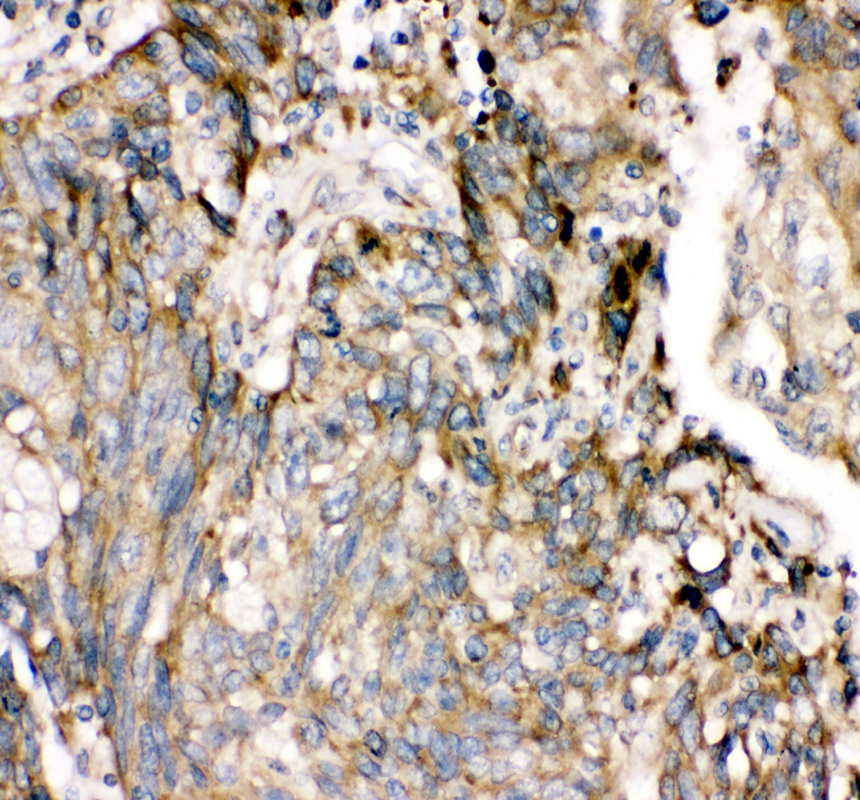

IHC analysis of SHP2/PTPN11 using anti-SHP2/PTPN11 antibody (PB9675).

SHP2/PTPN11 was detected in a paraffin-embedded section of human lung cancer tissue. The tissue section was incubated with rabbit anti-SHP2/PTPN11 Antibody (PB9675) at a dilution of 1:200 and developed using HRP Conjugated Rabbit IgG Super Vision Assay Kit (Catalog # SV0002) with DAB (Catalog # AR1027) as the chromogen.